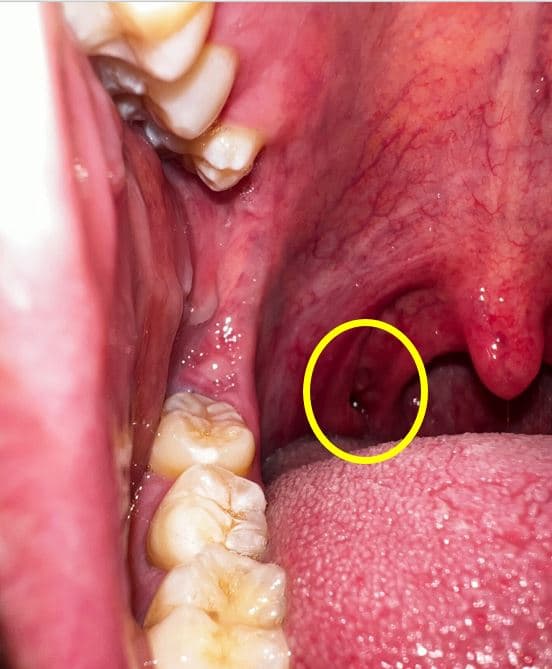

어느순간부터 편도쪽에 이질감과 함께 편도결석의 악취가 느껴져 핸드폰으로 촬영을 해봤습니다.

확인결과 목구명 편도 쪽에(아래사진의 목구멍편도 좌측 구멍) 구멍이 있습니다.

이상없을까요 ?